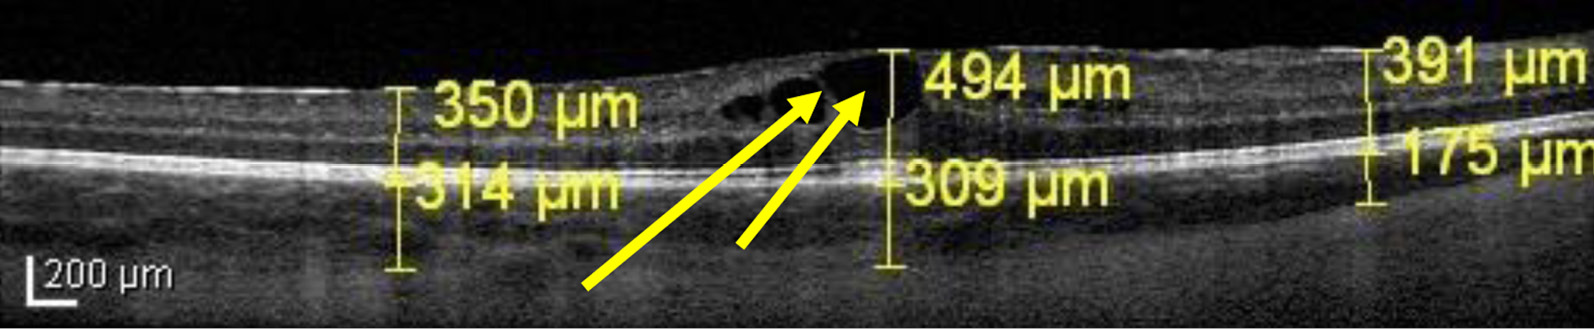

Утолщение сетчатки было зарегистрировано у пациентов с активным увеитом в 83% наблюдений, с вялотекущим — в 71%, с субактивным — в 55%, и было, очевидно, обусловлено накоплением в ней жидкости (отеком). При качественном анализе явный диффузный макулярный отек (утолщение сетчатки с наличием в ней мелких кистовидных полостей по типу «губки») был выявлен нами у 7 пациентов (26 наблюдений, 24%) (рис. 1), кистовидный (выраженное утолщение сетчатки за счет формирования кистовидных полостей большого размера) — у 2 пациентов (3 наблюдения, 3%) (рис. 2).

Рис. 2. Пациентка К. ОКТ макулы, активный увеит, кистовидный макулярный отек.

Примечание: Стрелками обозначены крупные кистовидные полости в зоне фовеа, за счет которых деформируется фовеолярный профиль. Толщина сетчатки увеличена.